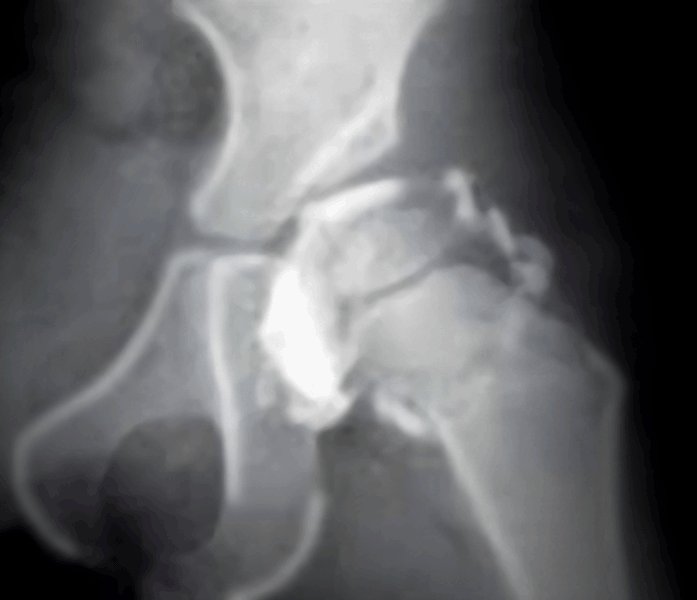

Evaluación radiológica de una articulación (muñeca, cadera, rodilla, hombro, tobillo) y tejidos circundantes (cartílago, ligamentos, bursa, cápsula articular) con la aplicación de un medio de contraste.

Para su realización, se ubica al paciente sobre la mesa de rayos con la articulación a evaluar expuesta. Se inyecta anestésico local en la piel. Se introduce una aguja en el espacio articular y se aspira líquido sinovial para su análisis y para minimizar la dilución del medio de contraste. A continuación se inyecta el medio de contraste en la cavidad articular. El paciente puede sentir una pequeña molestia. Es necesario después movilizar la articulación para distribuir el contraste. A continuación se obtienen radiografías en distintas posiciones.